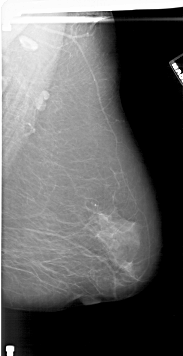

A_1805_1.RIGHT_MLO

RIGHT_MLO LINES 6406 PIXELS_PER_LINE 3286 BITS_PER_PIXEL 12 RESOLUTION 43.5 NON_OVERLAY